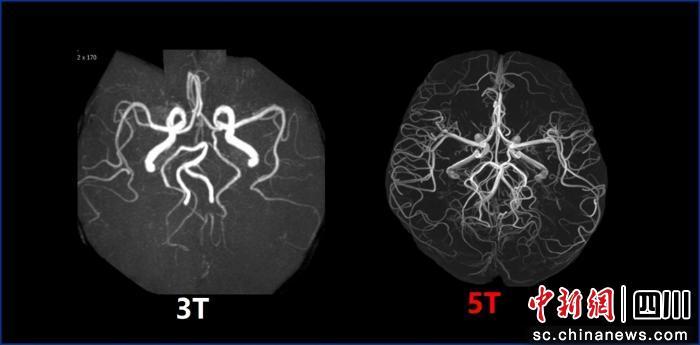

此前,臨床主流磁共振場強(qiáng)為1.5T和3.0T;國際上7.0T磁共振雖場強(qiáng)更高,但僅能實(shí)現(xiàn)頭顱及膝關(guān)節(jié)平掃,適用范圍較窄。此次投用的5.0T磁共振,相比3.0T成像清晰度大幅提升,可精準(zhǔn)識別1毫米乃至部分部位0.5毫米以下的微小病變或早期腫瘤,為疾病早診早治提供關(guān)鍵支撐;相較于7.0T,其適用場景更全面,可覆蓋全身成像,為中樞神經(jīng)系統(tǒng)、心血管系統(tǒng)、腹盆腔等多部位診斷提供高清影像依據(jù)。